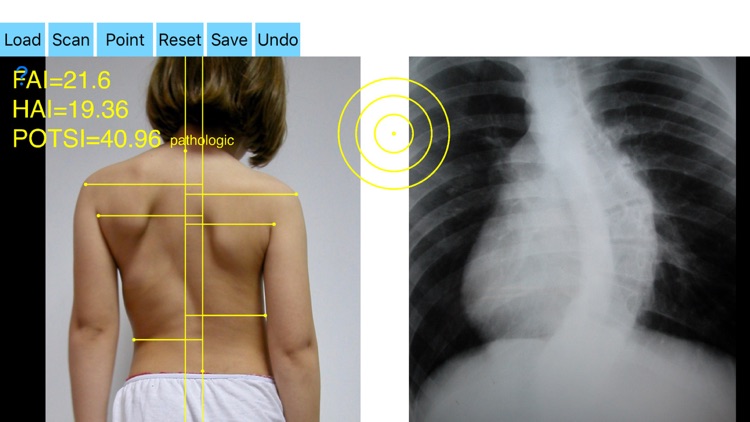

By visual inspection of the spine, asymmetry of the back is significant enough to suspect the existence of scoliosis in such cases, to evaluate spinal deformity an X-ray is ordered. Scoliometers could help evaluate the appearance of an asymmetric spine deformity with variable sensitivity and specificity but cannot substitute radiography. It is widely reported in the literature that significant correlations between radiographs and topographic parameters were found. Posterior Trunk Symmetry Index (POTSI) is a useful Index in the assessment of spinal deformity. POTSI Index is very sensitive in revealing any frontal plane asymmetry and could help identify moderate deformities which might otherwise be missed in clinics or physical examination. The Potsi Index is the sum two variables Height Asymmetry Index (HAI) and Frontal Asymmetry Index (FAI). Height asymmetry indexes are obtained as the sum of height differences of the shoulders, axillary folds, and waist creases, and it is normalized with the division of its value by the vertical distance from the C7 vertebra to the baseline of the gluteal cleft. The Potsi App calculates the Potsi Index according to the above mentioned developed topographic method (Suzuki N, Inami ) and offers a way to evaluate external back deformities with noninvasive technique. It is inexpensive and can be repeated indefinite times thus reducing unnecessary x-rays for normal anatomies and mild cases. The app helps the doctor in an outpatient setting to measure all the indexes in a blink of the eye by clicking few points.

-Securely import medical images directly from the camera or stored photos.

-by marking certain multiple anatomical points over the patients back the app can evaluate back’s symmetry in a few seconds. Eight specific points at the surface of the patient’s back are required. POTSI is relatively simple to measure, even on regular photography of the back. Ideal POTSI is zero, meaning full symmetry of the back surface. The App calculates all necessary elaborate formulas and after analysis the posterior trunk symmetry index(POTSI) is printed (normal value <10).